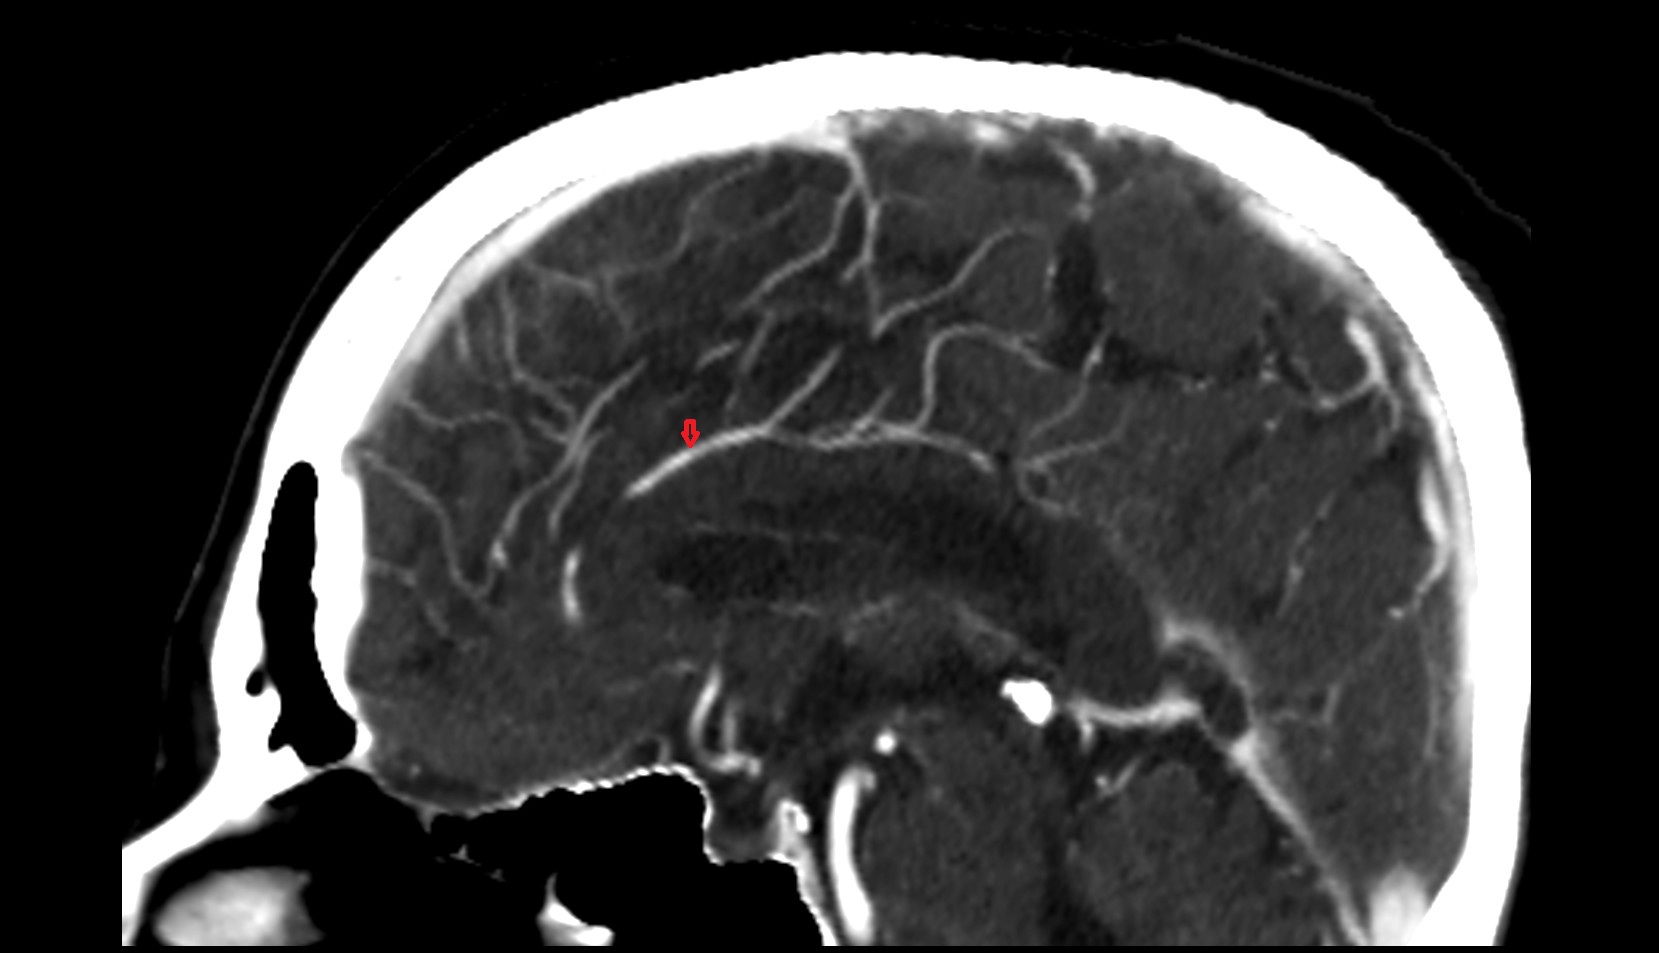

- Long medial striate artery